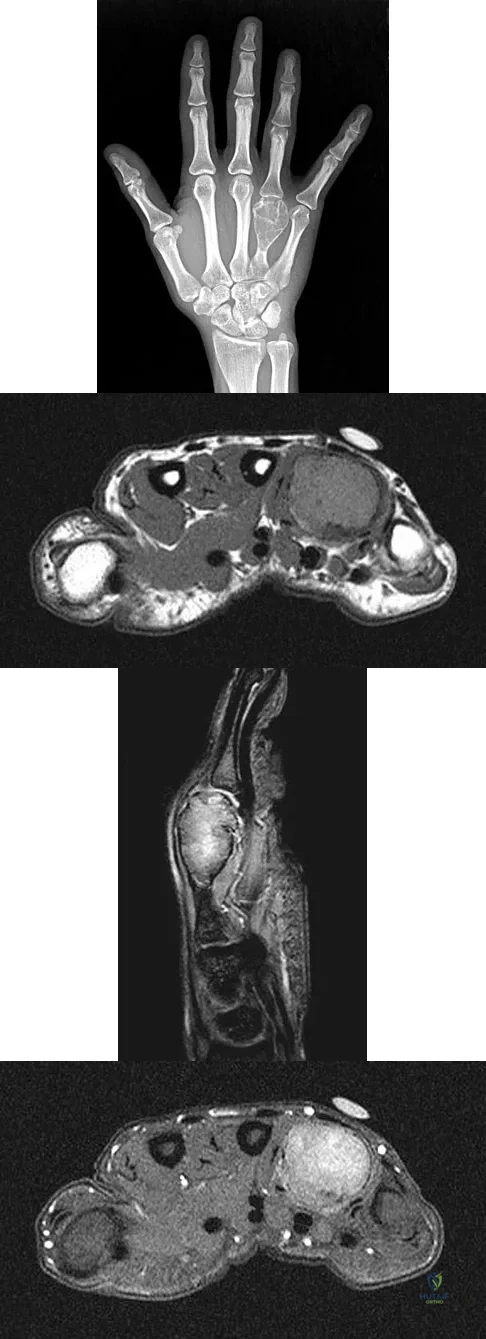

A 26-year-old man has had hand pain and progressive swelling in the knuckle for the past several months. He denies any trauma to the hand. The ring finger metacarpophalangeal joint is tender, and there is loss of motion in the digit. Figure 32a shows the radiograph and Figures 32b through 32d show the T1-weighted, T2-weighted, and gadolinium MRI scans, respectively. What is the most likely diagnosis?

Explanation